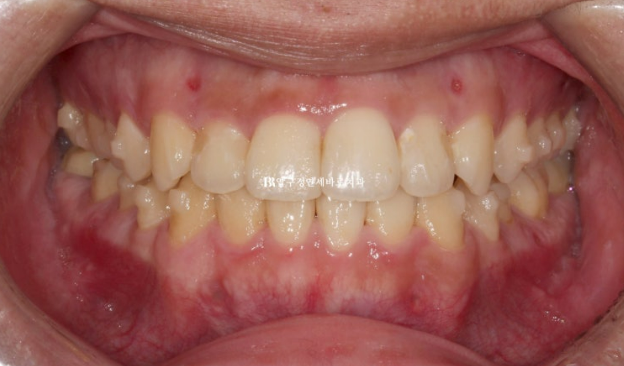

양악수술을 고려 중인 환자분이 내원하셨습니다.

양악수술 병원은 이미 여러군데 비교상담을 다녀오셨고

수술교정은 인비절라인으로 하고 싶다며 내원하셨습니다.

23.07

반대교합과 주걱턱이 심한 겨웅여서 양악수술 없이는 교정이 불가능한 상황입니다.

이 부분은 환자분도 알고계셨습니다.